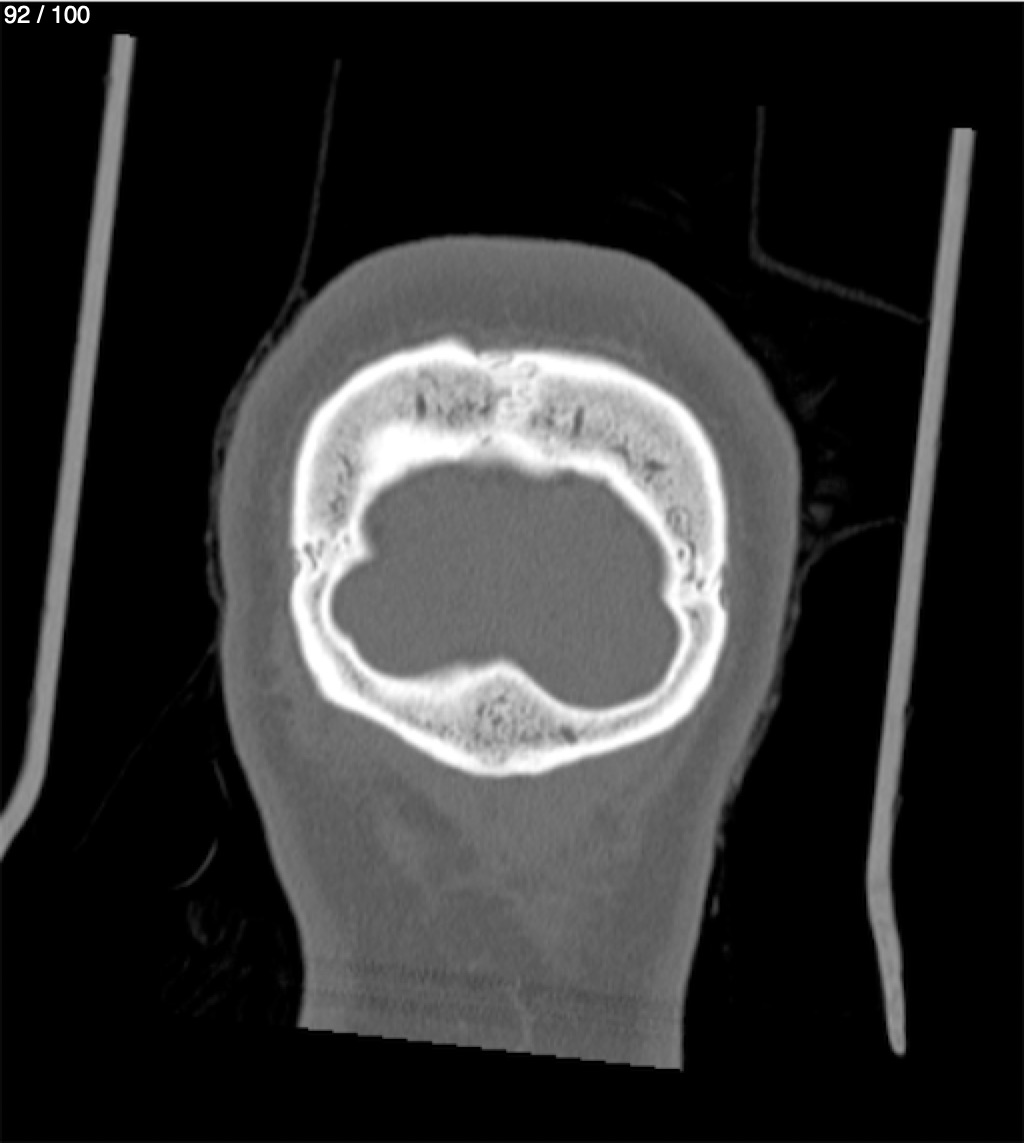

Reybet Garcia Fuentes 30A - T.C Craneo